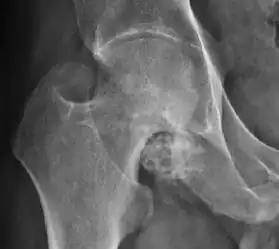

Plain radiography allows us to categorize the hip as normal or dysplastic or with impingement signs (pincer, cam, or a combination of both). Besides these, pathologic processes like osteoarthritis, inflammatory diseases, infection, or tumors can also be identified (Figure 1).[1]

Figure 1.

-

Radiography in normal hip -

X-ray in pincer impingement type of hip dysplasia -

X-ray of cam -

Hip in osteoarthritis -

Septic arthritis

- Osteoarthritis

In adults, one of the main indications for radiographs is the detection of osteoarthritic changes (Figure 1(e)). Nevertheless, radiographs usually detect advanced osteoarthritis that can be graded according to the Tönnis classifications. The grading system ranges from 0 to 3, where 0 shows no sign of osteoarthritis. Intermediate grade 1 shows mild sclerosis of the head and acetabulum, slight joint space narrowing, and marginal osteophyte lipping. Grade 2 presents with small cysts in the femoral head or acetabulum, moderate joint space narrowing, and moderate loss of sphericity of the femoral head. Grade 3 is the severest form of osteoarthritis, which manifests as severe narrowing of the joint space, large subchondral cyst with productive bone changes that may lead to deformity of the bone components of the joint, while secondary osteoarthritis due to calcium pyrophosphate deposition can be diagnosed when calcification of hyaline cartilage and fibrocartilage is detected.[1]

There are other pathological conditions that can affect the hip joint and radiographs help to make the appropriate diagnosis. Acute bacterial septic arthritis can be diagnosed by radiographs when a fast regional osteoporosis and destructive monoarticular process develops (Figure 1(f)). In case of tuberculous or brucella arthritis it is manifested as a slow progressive process, and diagnosis may be delayed.[1]

Synovial chondromatosis can be confidently diagnosed by X-ray when calcified cartilaginous chondromas are seen. However, other synovial proliferative processes, such as pigmented villonodular synovitis, require MRI for accurate diagnosis, although noncalcified synovitis can be suspected in radiographs by indirect signs, such as soft tissue swelling and/or erosions in the femoral head, femoral neck, or acetabulum (Figure 7).[1]